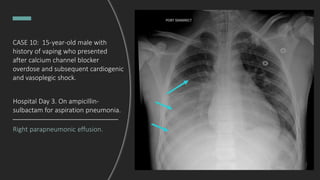

CASE 10: 15-year-old male with

history of vaping who presented

after calcium channel blocker

overdose and subsequent cardiogenic

and vasoplegic shock.

How has the film progressed?

Hospital Day 3. On ampicillin-

sulbactam for aspiration pneumonia.

Right parapneumonic effusion.